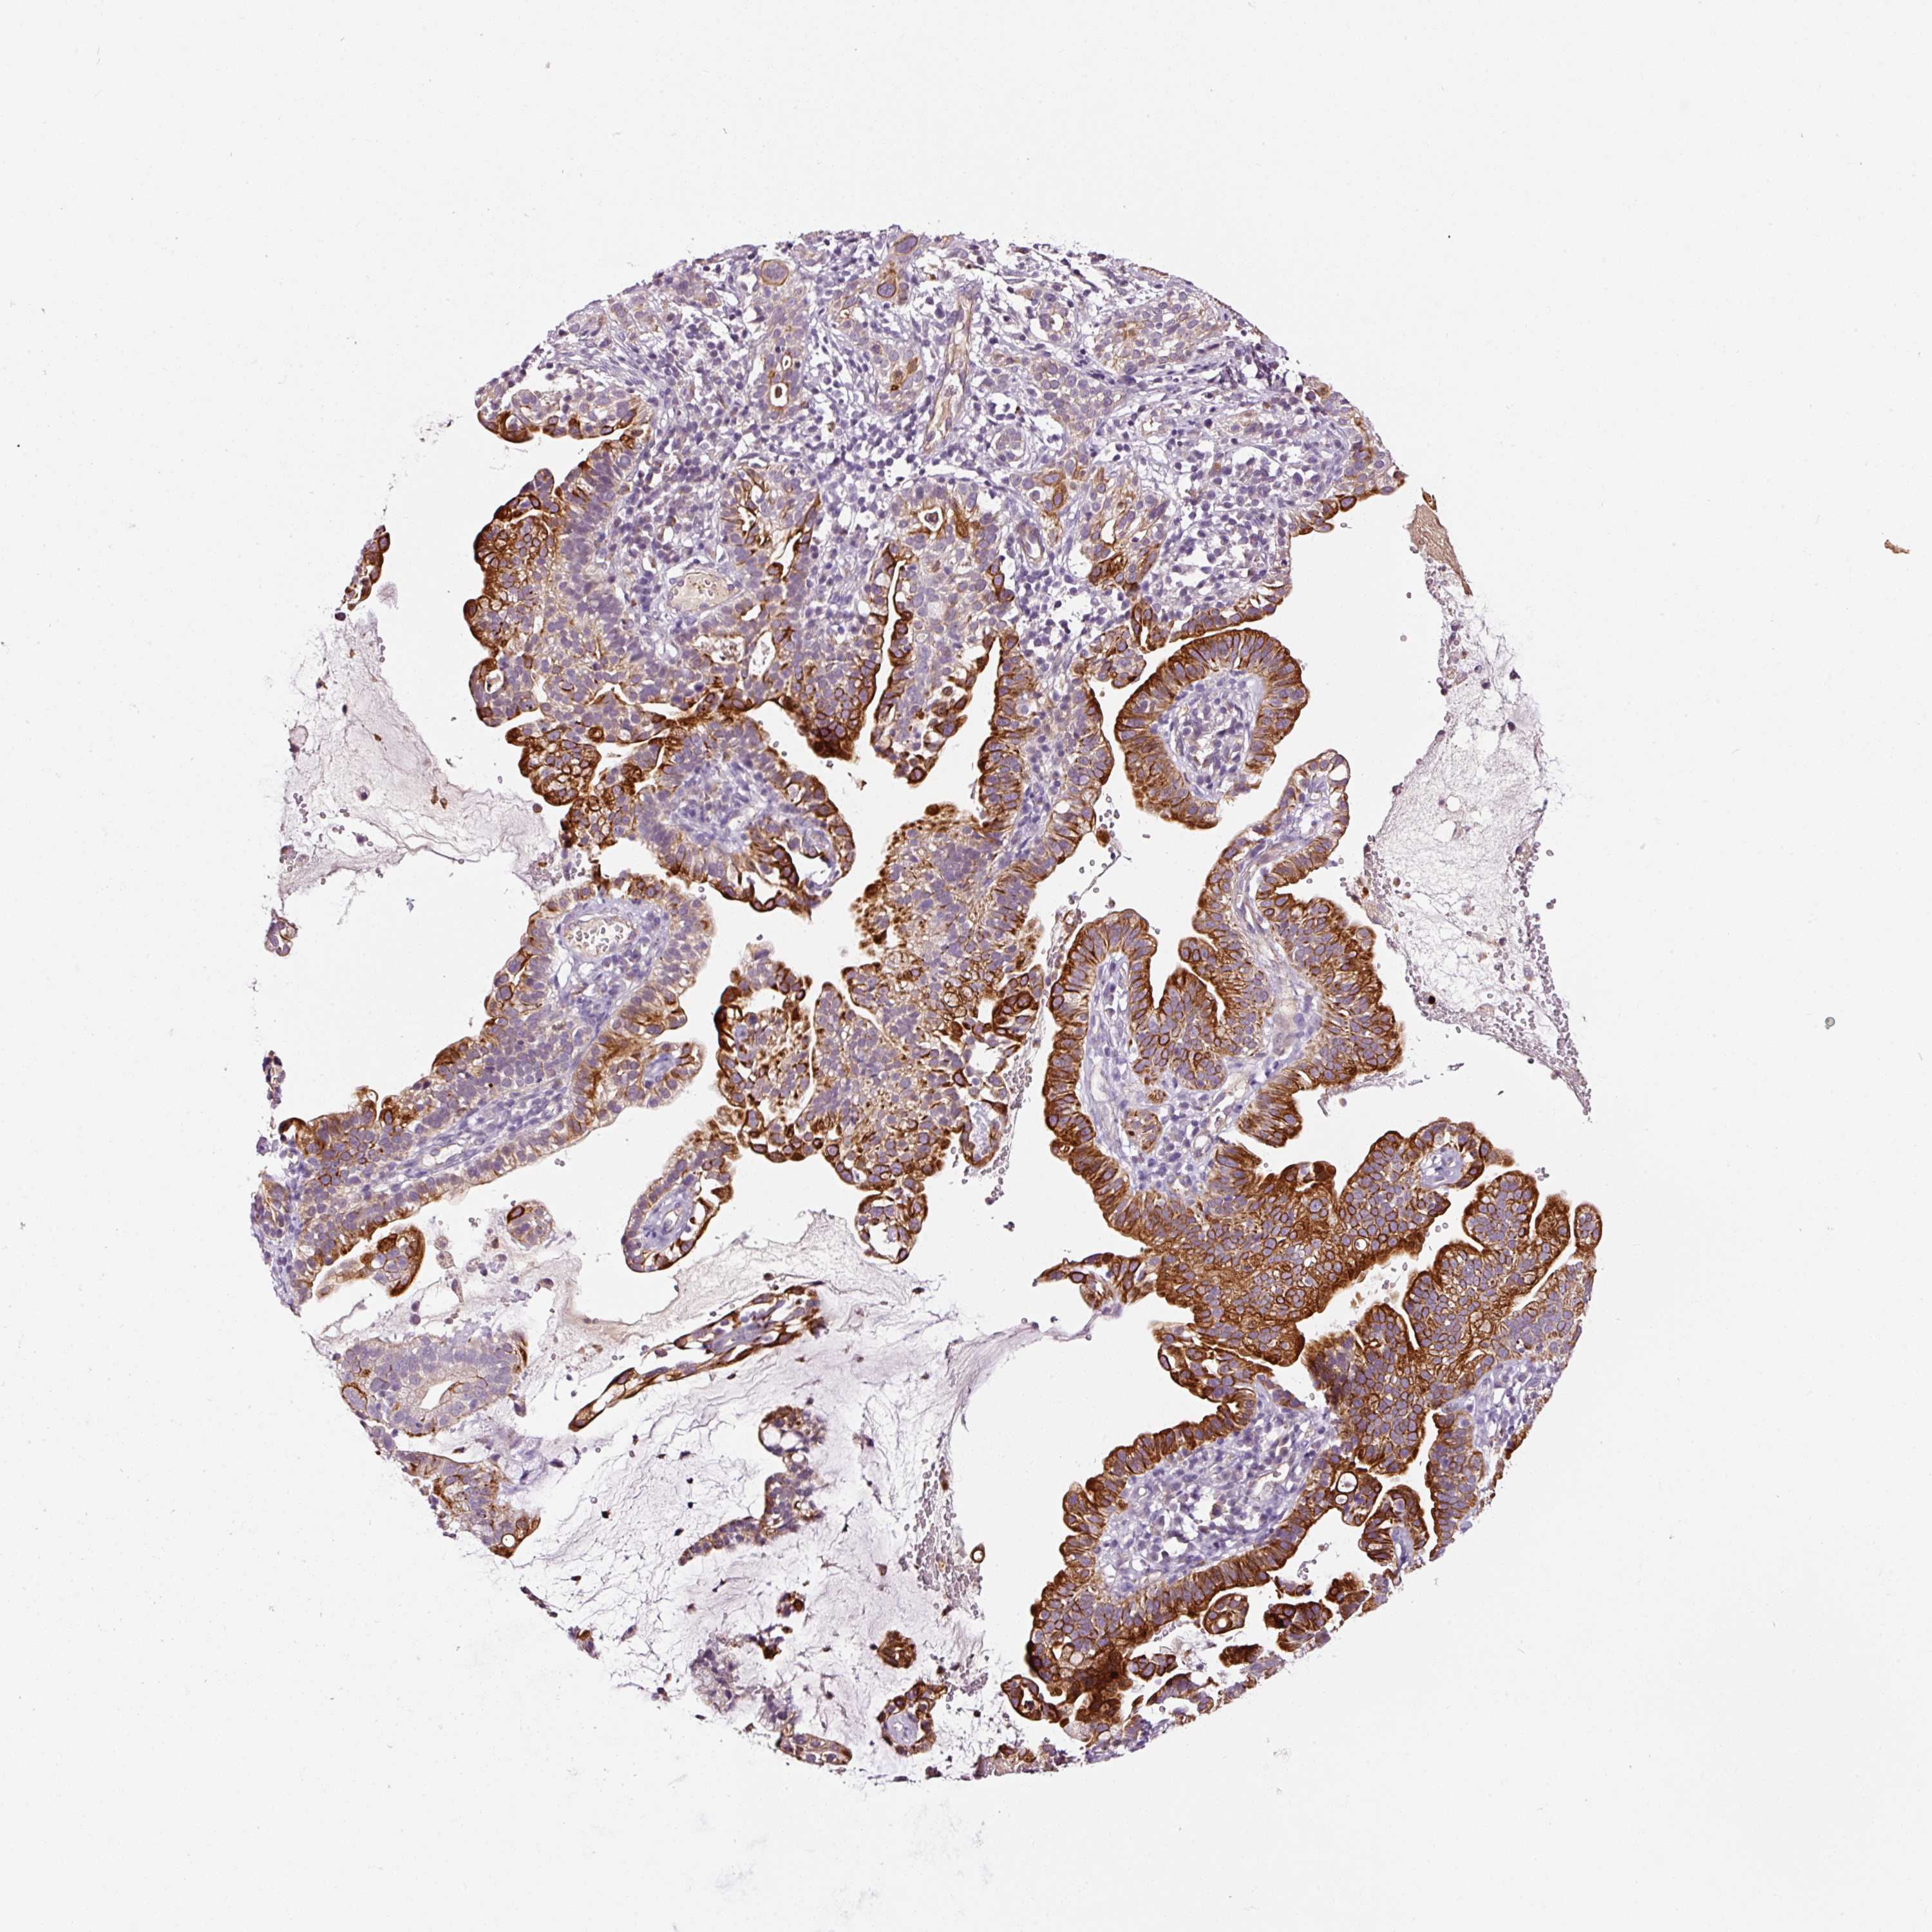

CERVICAL CANCER - Protein expressioni

A mouse-over function shows sample information and annotation data. Click on an image to view it in a full screen mode. Samples can be filtered based on level of antibody staining by selecting one or several of the following categories: high, medium, low and not detected. The assay and annotation is described here.

Note that samples used for immunohistochemistry by the Human Protein Atlas do not correspond to samples in the TCGA dataset.

Antibody stainingi

Antibody staining in the annotated cell types in the current human tissue is reported as not detected, low, medium, or high, based on conventional immunohistochemistry profiling in selected tissues. This score is based on the combination of the staining intensity and fraction of stained cells.

Each image is clickable and will lead to virtual microscopy that enables deeper exploration of all samples and also displays staining intensity scores, fraction scores and subcellular localization as well as patient and tissue information for each sample.

Antibody HPA049395

Antibody HPA053288

Staining

High

Medium

Low

Not detected

Intensity

Strong

Moderate

Weak

Negative

Quantity

>75%

75%-25%

<25%

None

Location

Nuclear

Cytoplasmic/membranous

Cytoplasmic/membranous,nuclear

Squamous cell carcinoma, NOS

Adenocarcinoma, NOS